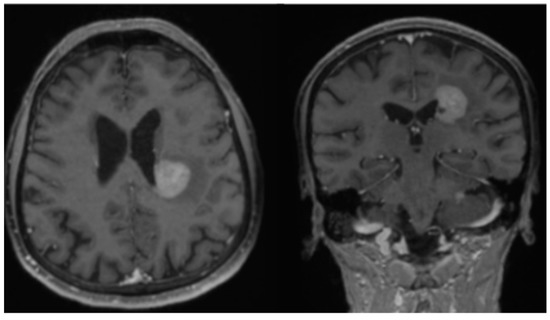

2. Case Report